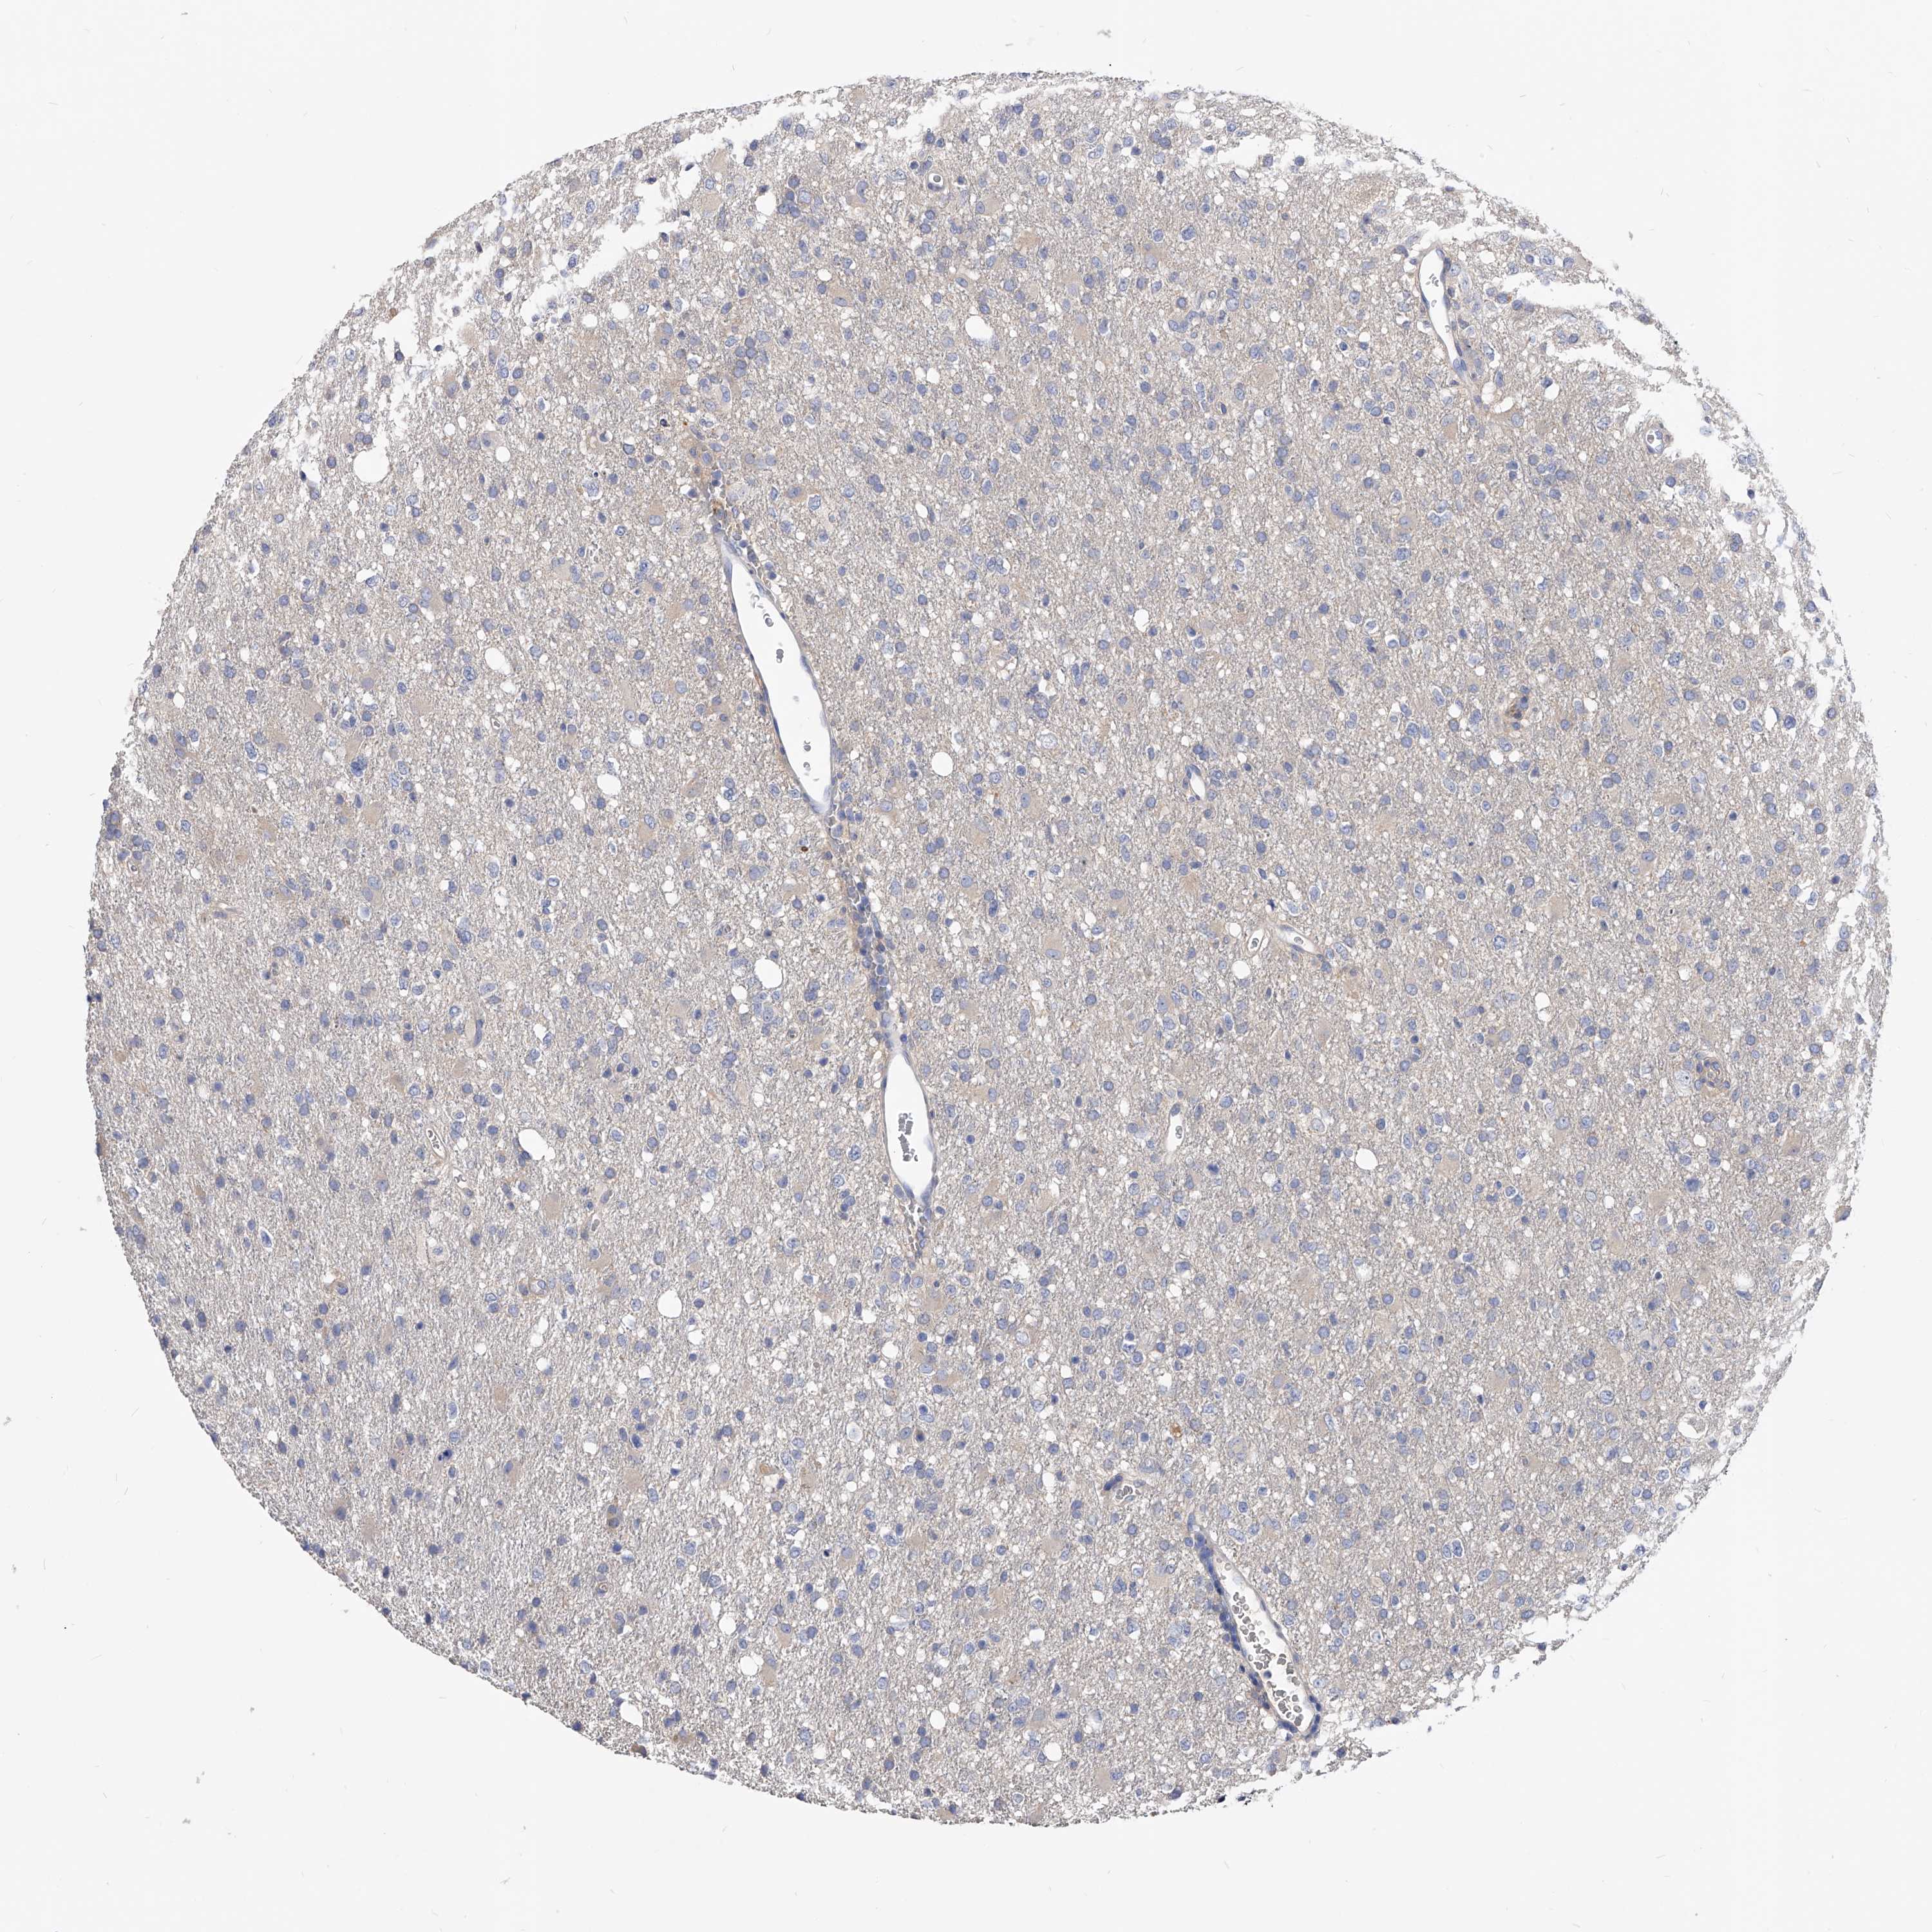

GLIOMA - Protein expressioni

A mouse-over function shows sample information and annotation data. Click on an image to view it in a full screen mode. Samples can be filtered based on level of antibody staining by selecting one or several of the following categories: high, medium, low and not detected. The assay and annotation is described here.

Note that samples used for immunohistochemistry by the Human Protein Atlas do not correspond to samples in the TCGA dataset.

Antibody stainingi

Antibody staining in the annotated cell types in the current human tissue is reported as not detected, low, medium, or high, based on conventional immunohistochemistry profiling in selected tissues. This score is based on the combination of the staining intensity and fraction of stained cells.

Each image is clickable and will lead to virtual microscopy that enables deeper exploration of all samples and also displays staining intensity scores, fraction scores and subcellular localization as well as patient and tissue information for each sample.

Antibody HPA029700

Antibody HPA029701

Antibody HPA029702

Antibody HPA029703

Staining

High

Medium

Low

Not detected

Intensity

Strong

Moderate

Weak

Negative

Quantity

>75%

75%-25%

<25%

None

Location

Nuclear

Cytoplasmic/membranous

Cytoplasmic/membranous,nuclear

Glioma, malignant, High grade

Glioma, malignant, Low grade

Glioblastoma, NOS